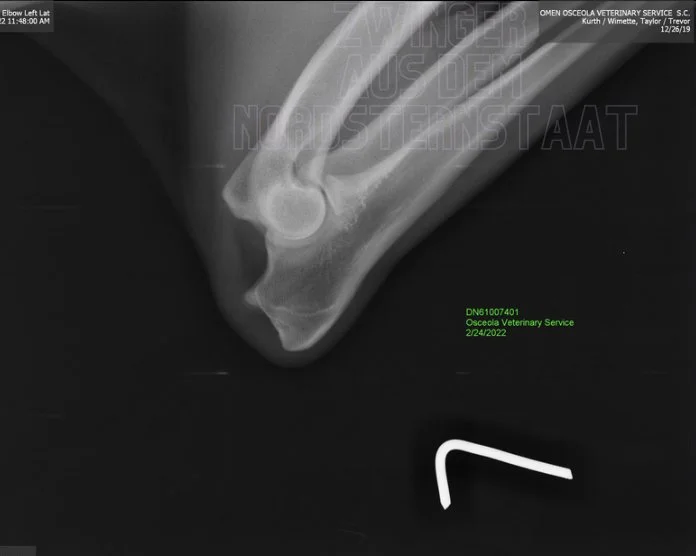

Omen is OFA Normal Elbows